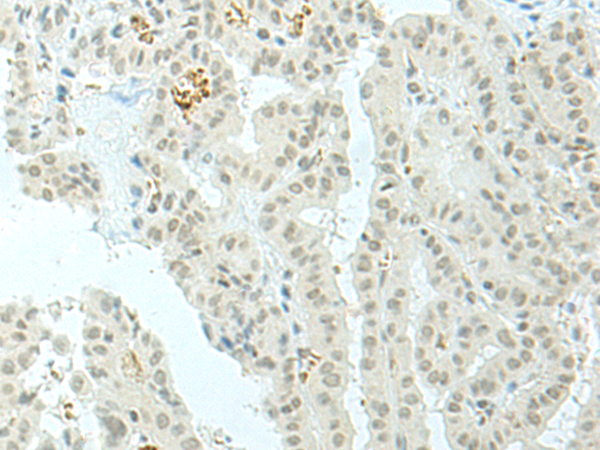

IHC positive control: |

Human lung cancer and Human thyroid cancer |

IHC Recommend dilution: |

30-150 |